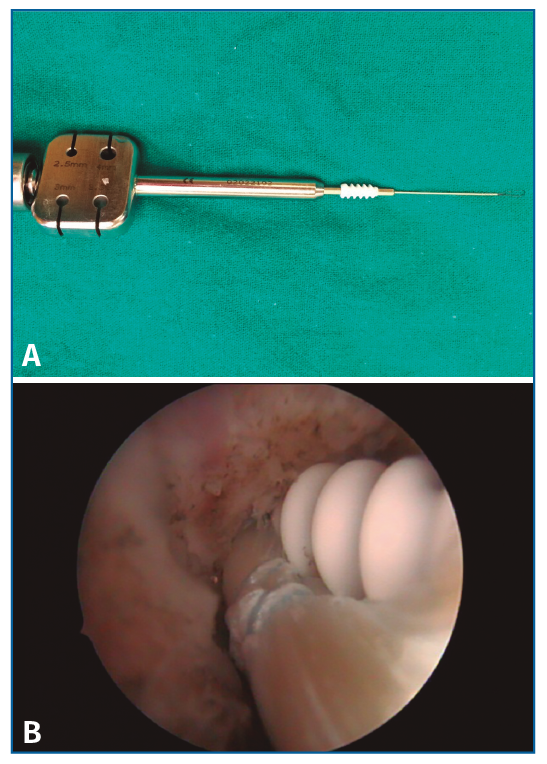

El material utilizado para esta técnica consta de: 2 tornillos de biotenodesis de 5 × 15 mm de Arthrex y artroscopio de 4,5 mm.

Empezamos con el túnel peroneal. Se coloca el tobillo en posición neutra y la dirección de la aguja guía es anteroposterior, con una inclinación de 5° de medial a lateral y paralela a la planta del pie(8). Se realiza un túnel ciego de 5 × 15 mm en la zona de inserción peroneal del LPAA.

A continuación, realizamos el túnel a nivel del astrágalo, desde el portal accesorio, a nivel de la inserción del LPAA en el astrágalo. Se coloca el tobillo en posición neutra y la dirección de la aguja guía es de lateral a medial, de proximal a distal, con una inclinación de 5-10° y de anterior a posterior con una inclinación de 5°. Se realiza un túnel ciego de 5 × 25 mm que nos va a permitir dar la tensión necesaria a la plastia (Figura 5).

Una vez realizados los 2 túneles, desde el portal anterolateral se inserta el tornillo de biotenodesis de 5 × 15 mm con la plastia colocada hasta la punta del destornillador y se inserta el tornillo siguiendo la técnica (Figura 6).

Figura 6. Tornillo de biotenodesis con la plastia colocada y lista para su introducción.